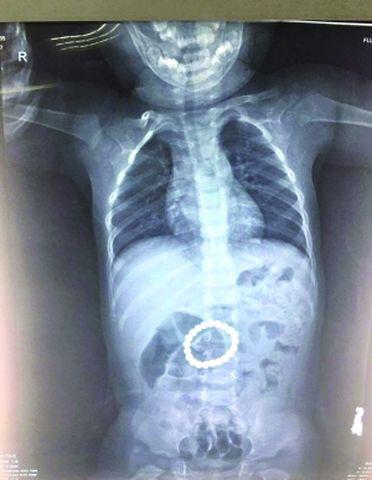

Theo phóng viên của tờ Beijing Morning Post đưa tin, từ phim X-quang có thể nhìn thấy, trong bụng của đứa trẻ có hơn 20 hạt nam châm xâu thành một chuỗi có đường kính vài mm.

Ảnh chụp X-quang của cậu bé 14 tháng tuổi